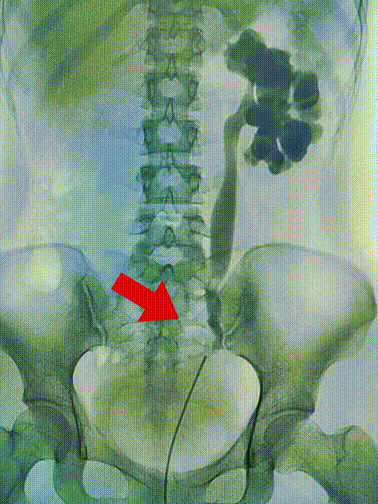

吴女士术前造影检查